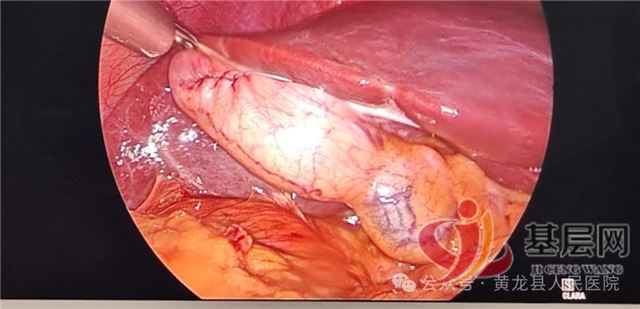

中国基层网讯(通讯员:郝雪茹)近日,黄龙县人民医院外科腔镜手术再传佳讯,在唐都医院肝胆外科帮扶专家贺小军带领下,成功为一名29岁胆囊结石患者顺利完成我院首例腹腔镜下保胆取石术,在最大程度减少创伤的基础上为患者保留了完整胆囊及其功能,患者术后恢复良好。手术的成功实施填补了县域内腔镜技术在胆囊结石疾病治疗领域的空白,同时标志着黄龙县人民医院外科微创治疗再上新台阶。

为尽早减轻患者疼痛,让患者得到精准高效救治,方继荣主任迅速组织全科医务人员讨论治疗方案,并邀请唐都医院肝胆外科帮扶专家贺小军参加会诊,经过多次、详细、周密的研究讨论,结合患者自身意愿,最终制定出详细周密的手术方案,告知患者及家属治疗方案,取得同意后,在手麻科配合下,顺利为患者实施“腹腔镜下保胆取石术”。手术顺利,达到了术前预期效果,术后患者入住外科无痛病房,在外科医务人员的精心治疗及优质护理下,恢复良好,术后1天即可下地活动、进少量易消化食物,目前已康复出院。患者及家属对手术和住院感受非常满意,为表达对贺小军专家和外科全体医护人员的感谢,出院后特意制作一面写有“医生仁心尽心尽责、护士有爱堪比南丁”字样的鲜红锦旗送到外科病区。

相比传统开腹手术,腹腔镜下保胆取石具有手术视野清晰、操作时间短、创伤小、术中出血少、疼痛轻及恢复快等诸多优点,且其既保留了胆囊及其功能,又取净结石,减轻了临床症状,充分展示了腹腔镜下保胆取石术的优势。